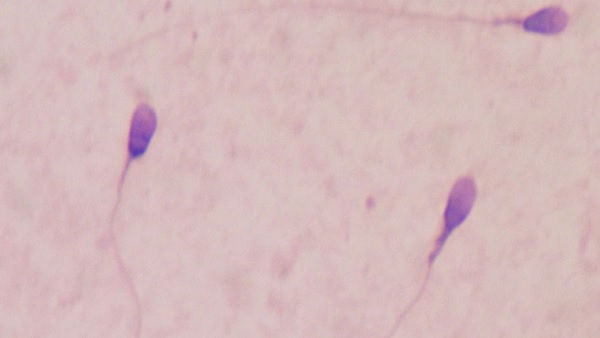

Air pollution कर रहा है Sperms की क्वालिटी खराब, नए शोघ में बड़ा खुलासा

शंघाई, 18 फरवरी। वायु प्रदूषण केवल भारत के लिए ही नहीं बल्कि पूरे विश्व के लिए बड़ी समस्या बना हुआ है। वायु् प्रदूषण से अभी तक लोगों को सांस की बीमारियों से दो-चार होना पड़ता था लेकिन अब ताजा शोध में एक चौंकाने वाली बात सामने आई है जिसने शोधकर्ताओं के होश उड़ा दिए हैं। चीन का नया शोध कहता है कि वायु प्रदूषण से पुरुषों की स्पर्म की क्वालिटी प्रभावित होती है।

चीन के साइंस Journal में प्रकाशित शोध में कहा गया है कि Air pollution शुक्राणुओं की संख्या और गति को प्रभावित कर रहा है। हवा में मौजूद छोटे प्रदूषण के कण बड़े वाले प्रदूषण के कण से ज्यादा खतरनाक है। स्पर्म के लिए 10 माइक्रोमीटर वाले पैरामीटर से ज्यादा खतरनाक 2.5 माइक्रोमीटर वाले पैरामीटर हैं। जो कि एस्थेनोजोस्पर्मिया को बढ़ावा देते हैं। आपको बता एस्थेनोजोस्पर्मिया का मतलब है पुरुष शुक्राणु में गतिशील शुक्राणुओं की संख्या में कमी, ये बांझपन का कारण होता है, क्योंकि गतिहीन शुक्राणु अंडे को निषेचित नहीं कर पाता है।

इस शोध से बात साफ हो गई है कि Air pollution पूरी आबादी की प्रजनन क्षमता पर खराब असर डाल रहा है। शंघाई में Tongji University के स्कूल ऑफ मेडिसिन के शोधकर्ताओं ने 340 चीनी शहरों के कुल 33,876 पुरुषों पर ये शोध किया है। इन सभी लोगों की उम्र 30 साल से 35 साल के बीच में थीं। शोधकर्ताओं का दावा है कि वायु प्रदूषण वीर्य की गुणवत्ता और शुक्राणु की गतिशीलता पर प्रतिकूल प्रभाव डाल सकता है, जिससे पुरुष प्रजनन दर प्रभावित हो सकती है।